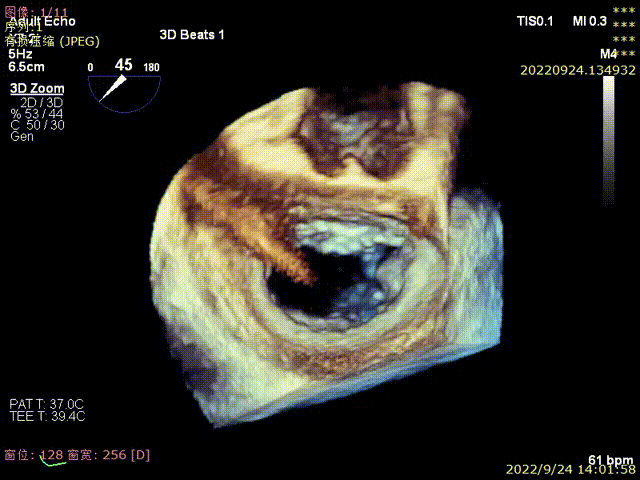

图3,由于患者反流位置位于3区偏交界,在MultiVue模式指导下进行操作

由于非2区病变患者瓣膜反流位置较偏,操作器械系统输送到达目标位置困难、同时食道超声与器械存在夹角,需要使用具有MultiVue(三维重建)功能的超声机器,且手术中缠绕腱索的风险增大,该类患者往往在筛选期就被拒绝难以得到救治,而ValveClamp系统通过心尖操作,选取最佳穿刺点,仅40分钟就植入2枚夹子,消除大部分反流达到满意的手术效果,充分显示器械操作便利性、高效性